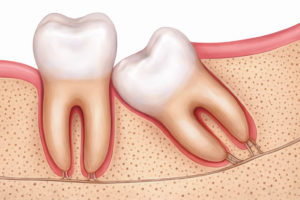

↑ 下顎前歯の叢生は、親知らずだけではなく、顎の骨の幅の変化など、色々な要因が影響を及ぼしています

↑ このように前に倒れていて、間に汚れが溜まりやすい場合は、注意が必要です

↑ 親知らずが第二大臼歯に接触し、歯根吸収を及ぼすことがあります(イメージ)